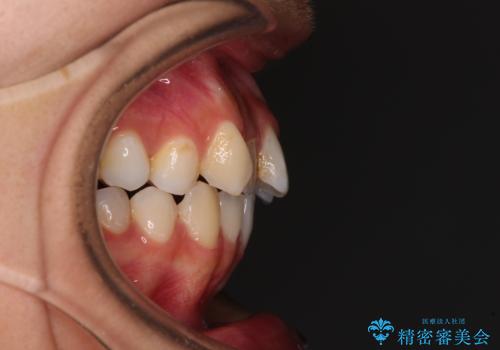

- 前歯のデコボコと口元の突出感を気にして来院された患者様です。

口元の突出感が認められ、更には左右で異なる咬合状態であったため、下顎右側は第二小臼歯を、左側は第一小臼歯を抜去することでバランスを取るような治療計画としました。

下顎の抜歯位置を左右で変えることで、最終的に上下正中をほぼ一致させることができました。